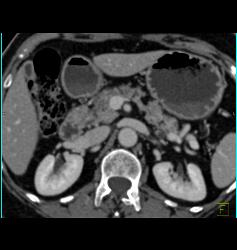

Intraductal Papillary Mucinous Neoplasm (IPMN) With Normal Splenic Artery and Vein